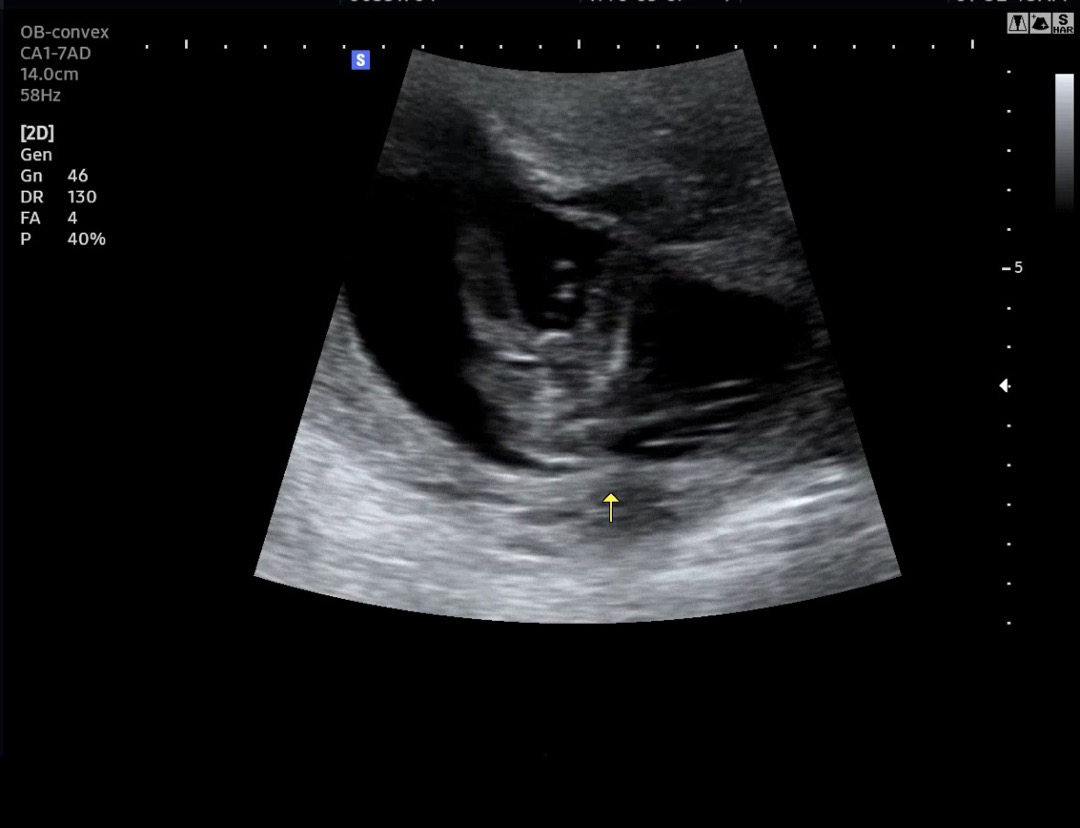

15주차 초음파사진인데 고수님들 한번만 봐주세요!!

이정도면 딸이겠죠???